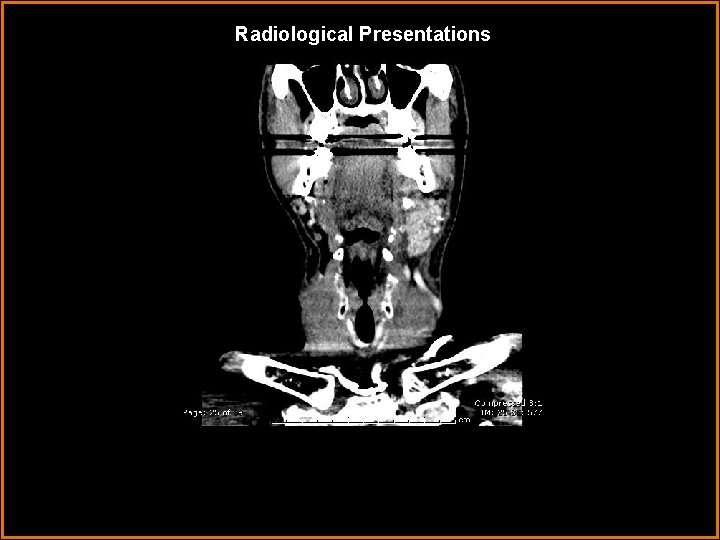

Radiological Presentations

Findings and Differentials Findings: Markedly enlarged, enhancing left submandibular gland with a large 1. 1 cm stone in Wharton’s duct. Differentials: • Submandibular venous vascular malformation – lobulated, heterogenously enhancing mass. • Sialosis – painless bilateral enlargement of salivary glands, usually the parotid glands. Associated with diabetes, obesity, and alcoholism. • Kuttner tumor – pseudomass of salivary gland associated with calcification.

Diagnosis Sialadenitis caused by sialolithiasis.